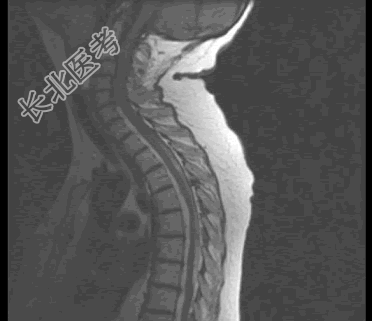

- 单项选择题患者,女, 68岁,头部剧痛伴左上肢无力半月余, 近两天发展为双下肢截瘫,请结合影像学检查, 选出最可能的诊断 ( )